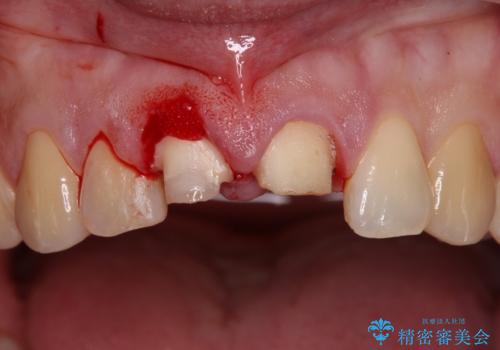

- 転倒により前歯を折ってしまったとのことで来院された患者様です。

右側の前歯は歯茎の中にまで及ぶ深い破折線があり、神経組織は既に失活していました。

左側の前歯は大きく歯冠が欠けてはいましたが、神経の生活反応が認められました。